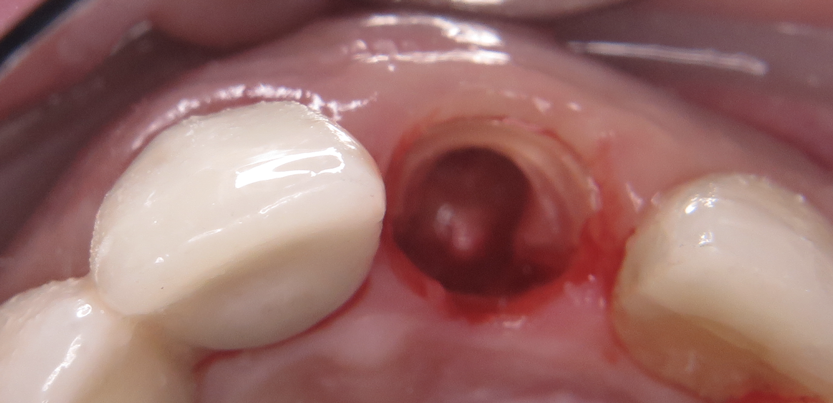

Case Study 1: Guided Implant Surgery in Conjunction With Partial Extraction Therapy

Evaluation of a single site can be simplified using the "triangle of bone" concept.14 In the author's practice, a 48-year-old male patient presented for a routine emergency recementation visit, at which time a root fracture was noted on the palatal side of the patient's root. The crown was temporarily recemented, CBCT imaging was performed (Figure 2), and the patient was evaluated for tooth replacement with a dental implant. A triangle was drawn in the cross-sectional CBCT image to determine the proper implant placement and analyze the future implant in a restorative-driven fashion.15 Careful evaluation of this cross-section revealed a thin buccal plate associated with the endodontically treated root. This finding indicated that the buccal wall would likely be fractured during extraction, which would lead to a buccolingual collapse16of the hard and soft tissues. To avoid this risk, partial extraction therapy, a technique used to preserve the buccal plate by carefully removing contents of the root and leaving the buccal segment,17-19 within the triangle of bone was planned.20

Fig 2. Triangle of bone. Outlining the available bone utilizing the

triangle of bone concept provides a design-making tree for the

clinician. Bisecting the triangle can aid in multiple aspects of

treatment planning, including implant positioning, selecting screwversus

cement-retained restorations, and grafting requirements,

among others.

Fig 4. The palatal portion of the root was sectioned and

extracted. The remaining portion of the root must be trimmed to level of the alveolar crest and shaped to allow for implant placement. Roughly

1 to 2 mm of tooth thickness remains, with the length proportional to the extracted segment. No apical contents should remain, as apical

infection may occur. It is imperative to debride the apical root segment prior to implant placement.